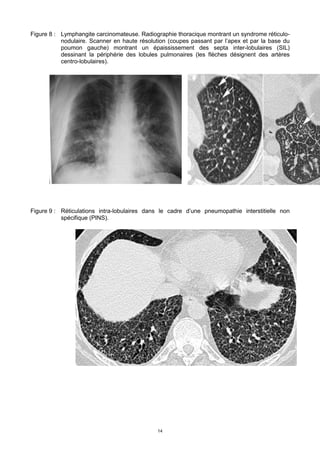

Figure 10 : Pneumonie organisée cryptogénique (POC) se traduisant par des condensations

bilatérales, de densité variable, à limites floues ou nettes, de localisation périphérique,

certains contenant un bronchogramme aérique. Le caractère migratoire (avec

disparition de certaines lésions et apparition d’autres lésions) est évocateur du

diagnostic.

Figure 11 : hémorragie alvéolaire se traduisant par des plages de verre dépoli diffuses (ou

généralement centrales)

Figure 12 : Plage de verre dépoli (adénocarcinome lépidique)